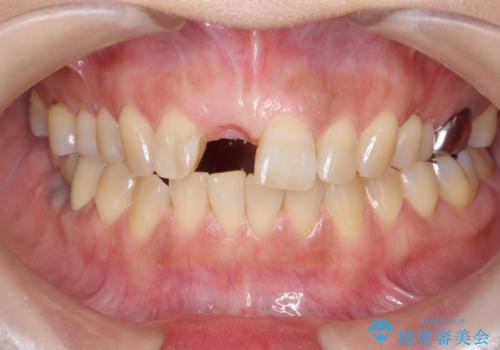

- 前歯を外傷により失い、審美性の改善を求めて来院されました。

横の歯を削る必要のあるブリッジ治療、着脱の必要な入れ歯に強い抵抗があったためインプラント治療を計画します。

審美的・機能的に良好な位置に埋入するには、骨量が十分ではなかったため骨の造成を併用したインプラント埋入外科手術を行います。